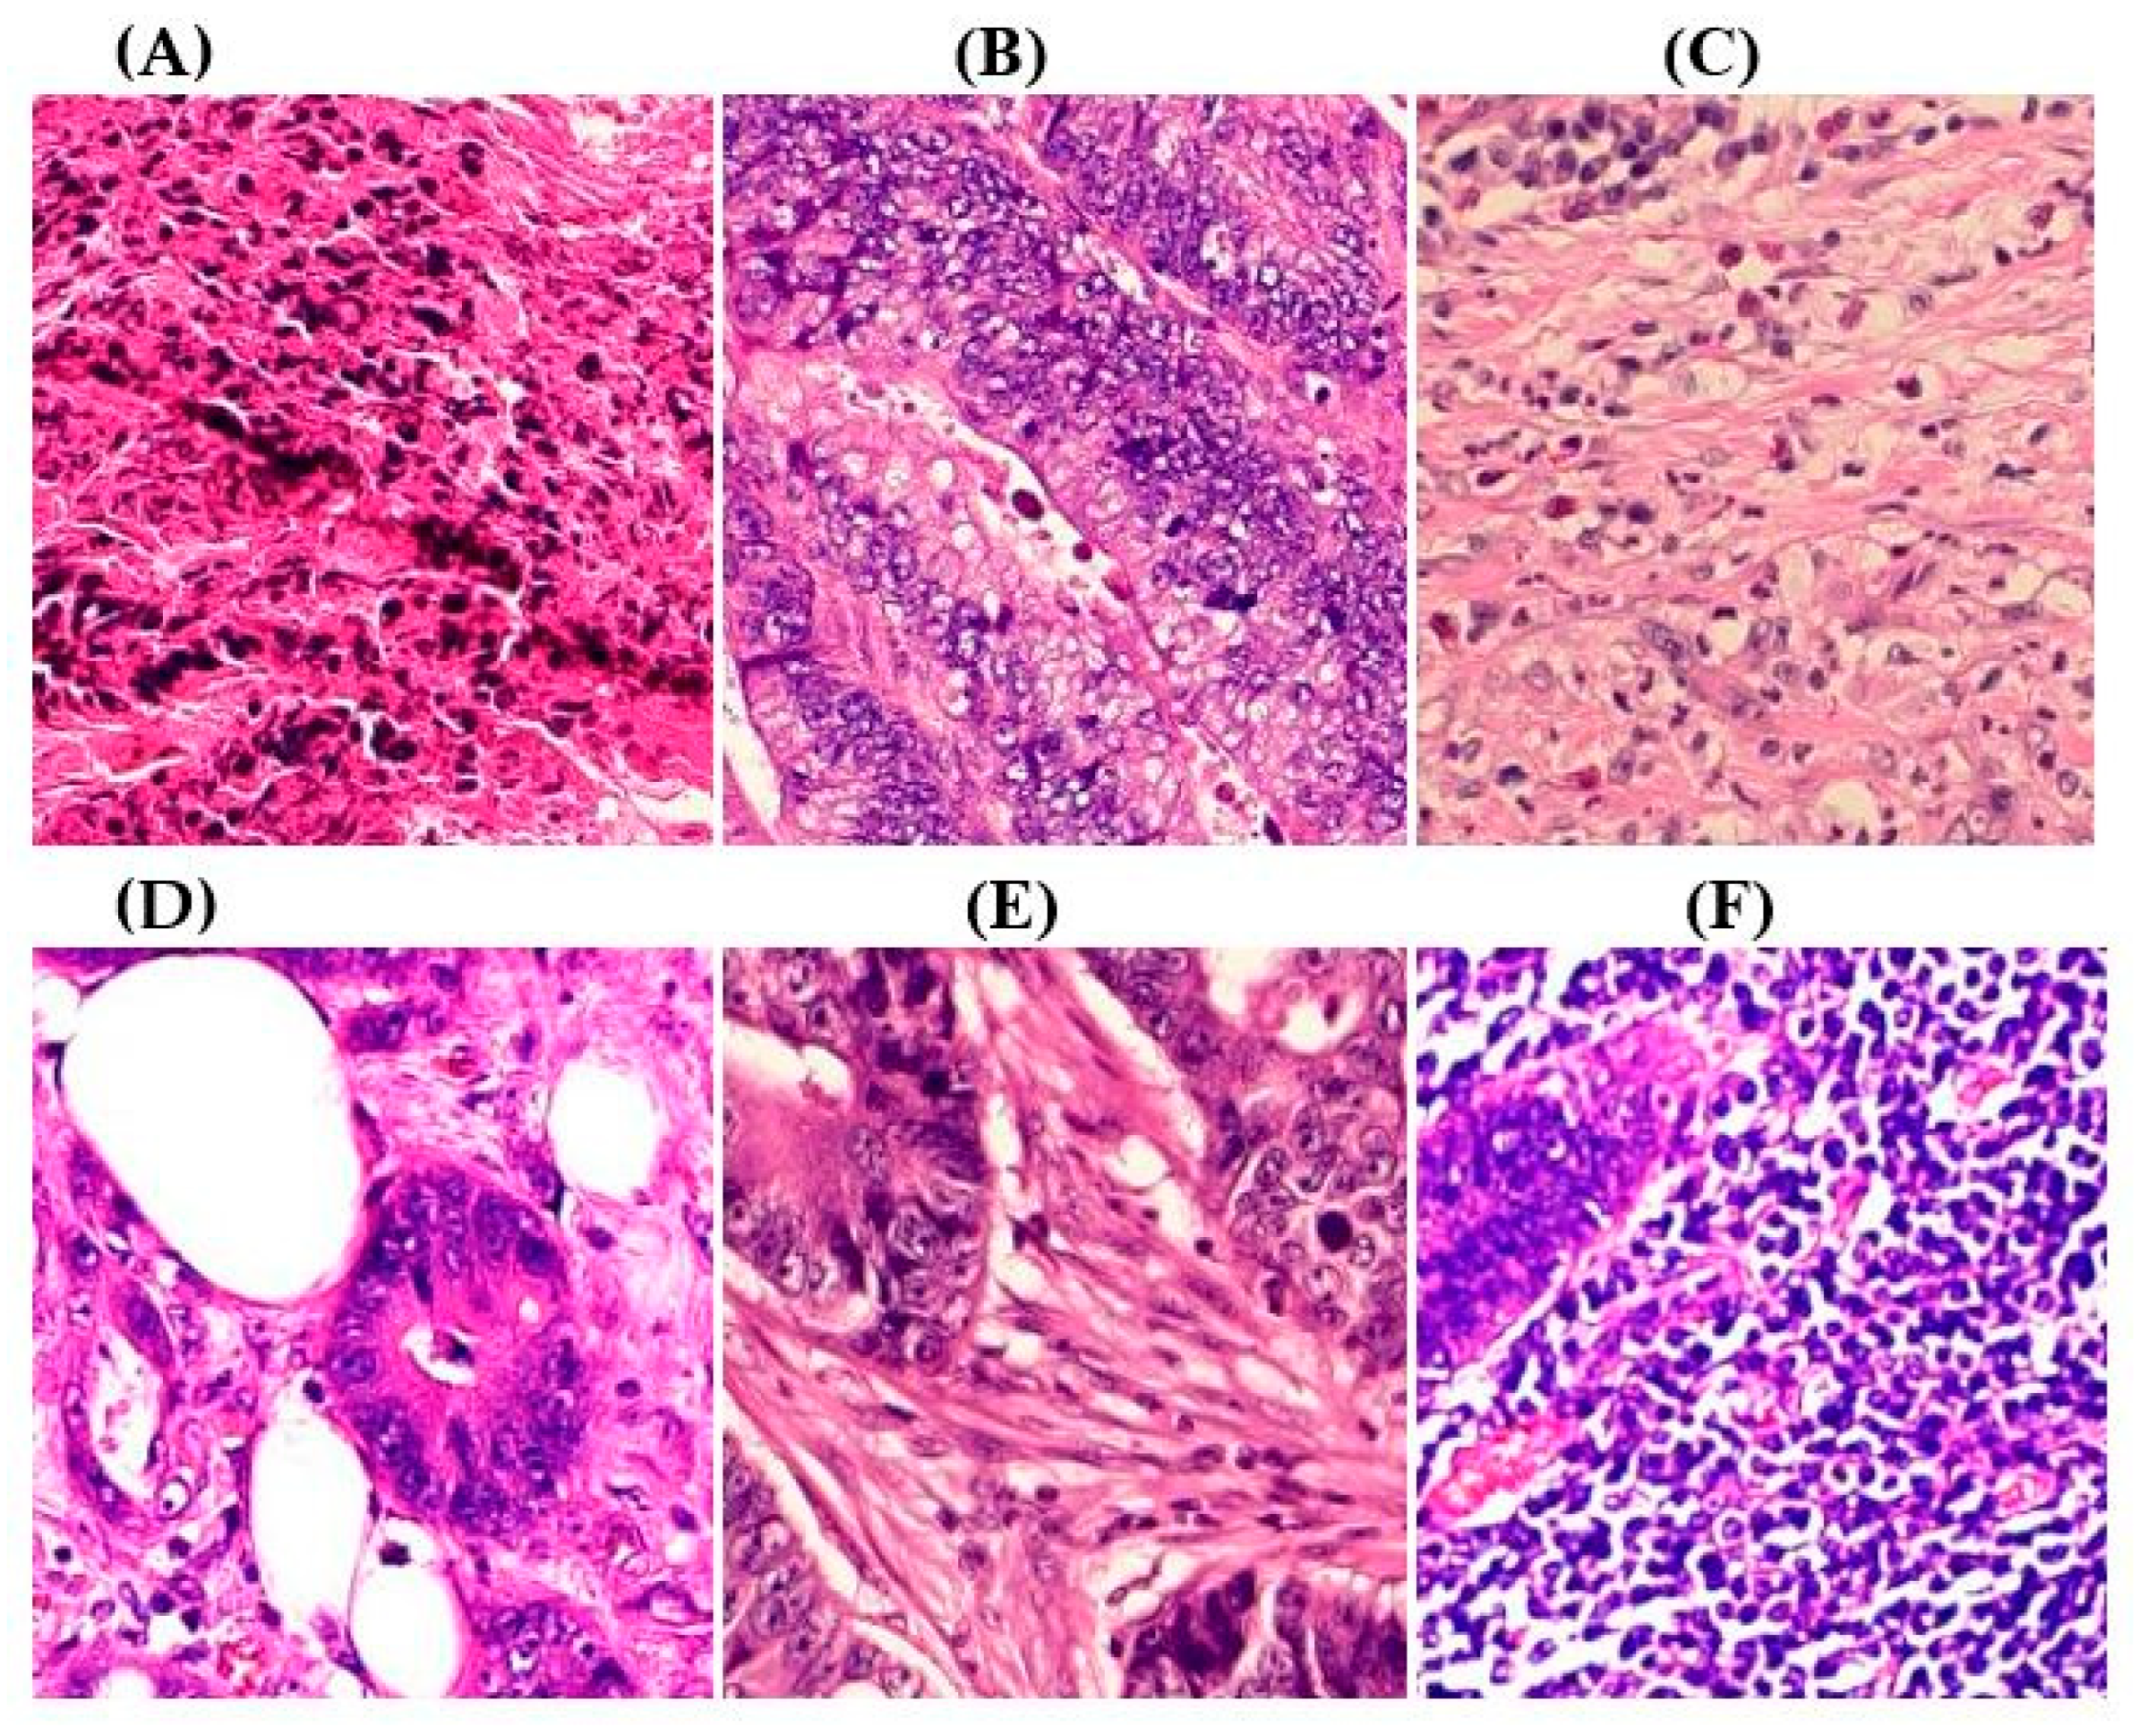

Related Work

2. Materials and Methods

2.2. CRC Histopathological Datasets and Preprocessing

3.2. Performance Comparison of Baseline Versus ADFMs

3.3. Proposed Model Performance Metrics by Class Across Six Datasets

3.4. Experimental Results